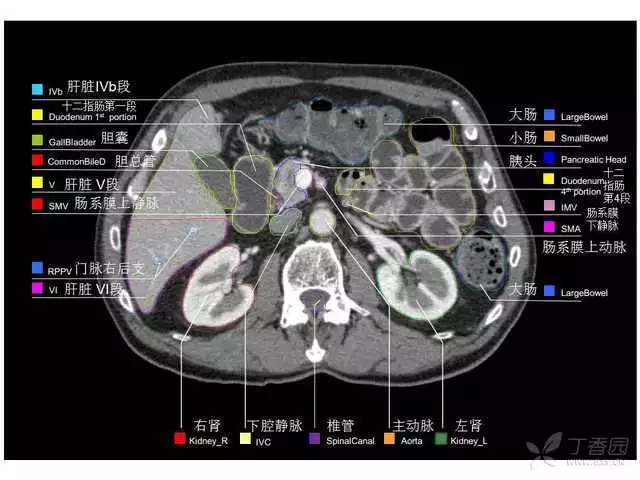

腹部肝脏高清CT断层的图谱

全腹部高清CT图谱,淋巴结彩色图谱,血管解剖图谱大汇总!

超声肝脏分叶及分段

肝脏分段和基本解剖学标志